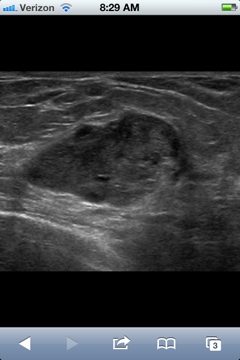

Over a month ago I found a lump in my left breast. I went to the doctor and he could feel it and instructed me to come back in a few weeks. I did. Lump still there. He scheduled an ultrasound for the following week (Thursday right before Eugene). I had to take my 4 year old daughter thinking it would be quick because I wasn’t really worried. The quick appointment turned into 2 hours of worry. They did the ultrasound, then I had to get a mammogram and then discuss the lump. Most of the characteristics seemed benign but there was enough suspicion to do a needle biopsy or take the lump out. Whoa. Wait. This was a lot to digest and try to keep calm with a hungry bored 4 year old.

I opted for the needle biopsy. We scheduled it for Tuesday.

The radiologist who did the procedure is a friend of ours and when I saw his concerned face I fell apart. He was great and as gentle as he could be. Being in the room with the ultrasound machine, my husband, and concerned physicians brought back all the memories and heartache with my pregnancies. I just wanted to be left the fuck alone! Be normal. Not have to worry. It seems just when life is almost so good you need to pinch yourself, that is when the other shoe drops. I knew it. Too good to be true. I just tried to maintain calm. I looked over at my poor husband and he was green in the face and looked pretty upset. He never looks upset. Ugh. I was so glad he was there to suffer with me support me. He’s pretty great.